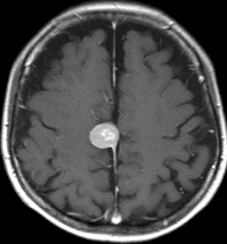

- 下のMRIは66歳の女性に脳ドックで偶然見つかった髄膜腫です.左の写真は1995年,右は2005年です。10年間で全く大きくなっていません